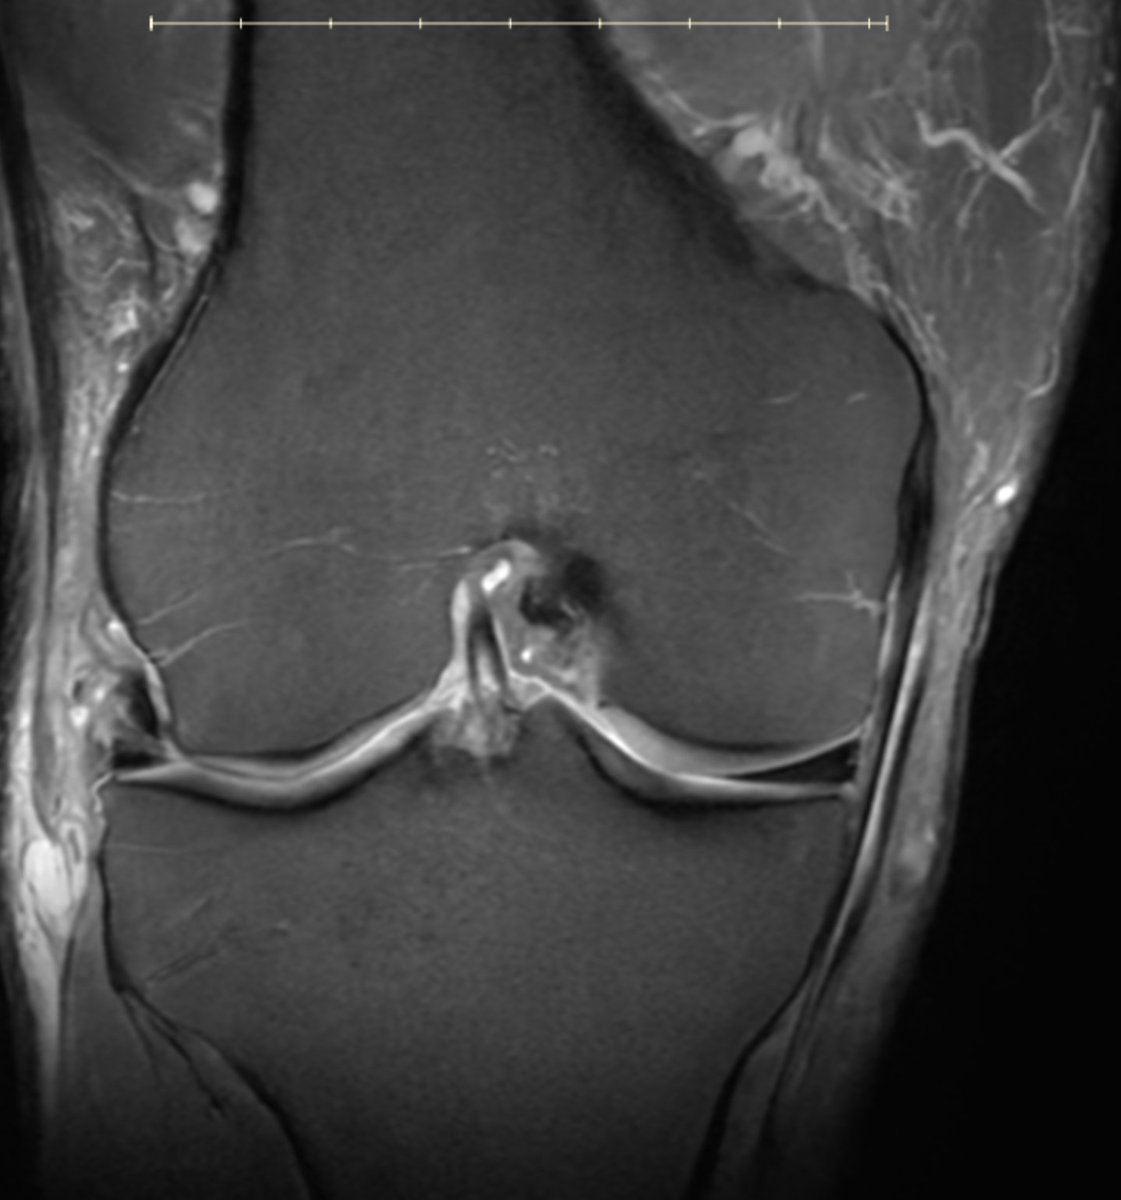

60 yo runner. Also lifts 3x/week. Stable lateral meniscus tear and a small cartilage defect for 10 years. New pain.. worse. Mostly anterior, anterolateral. Pain with loading, jumping, etc... but on landing, not the jump. in other words... axial load hurts.

New MRI: mostly anterior BME deep to PT insertion.

Stress reaction from the tendon or load??